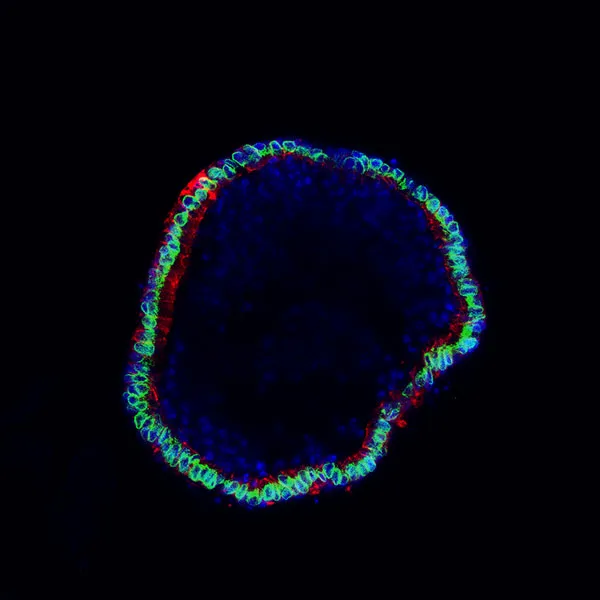

Organoid in cross section

How does Wnt signalling regulate tubular morphogenesis in the liver?

In many tissues tubes are required to transport factors from the site of production to site of effect. This is true in the liver, where from a discontinuous network of ducts, a complete biliary tree needs to form. How small regions of duct, which are specified in development grow and interconnect to form a complex network is of particular interest to us, particularly given the role of Wnts in these types of process in other tissues.